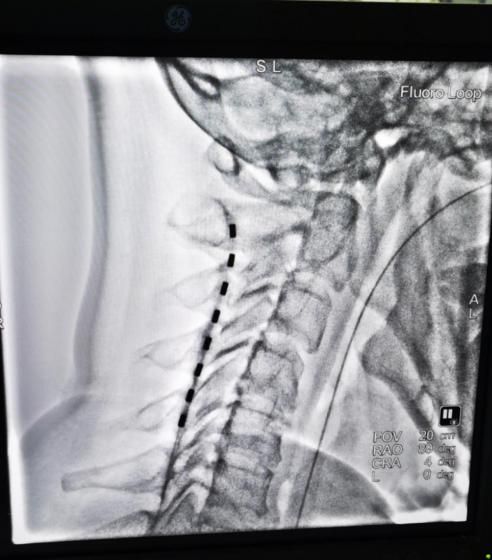

脊髓電刺激手術(shù)在黃銳副主任指導(dǎo)下,由張欲凱醫(yī)生主刀完成,術(shù)中在DSA設(shè)備下,將直徑1.3mm的電極,通過穿刺針植入到患者脊髓硬膜外腔直到目標(biāo)節(jié)段。陳巖副主任設(shè)定程控儀參數(shù),經(jīng)檢測(cè)置入電極工作正常。整個(gè)手術(shù)過程非常順利,患者狀態(tài)良好。